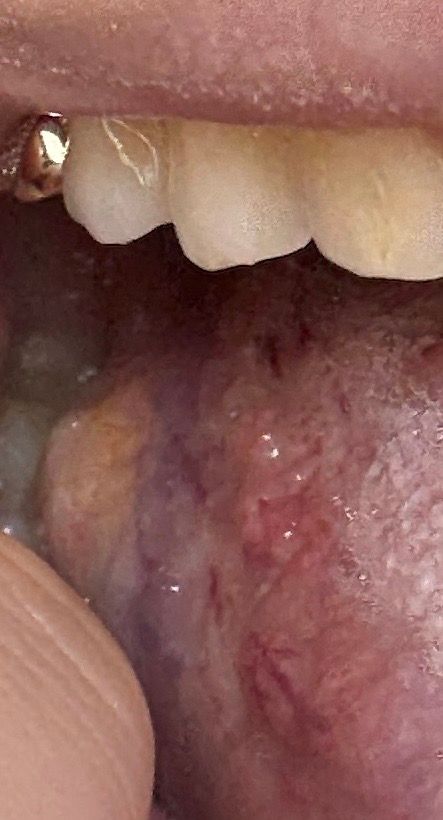

혀염증 좀 나아가는지 봐주세요!!!

사진으로는 정확한 진단 불가능하며 병원 방문하셔서 직접 육안으로 진료 보셔야 합니다

병변이 잘 안 보여요

말씀하신 내용 토대로는 나아진 거 같습니다 (병변으로 판단하게 아니라 말씀하신 내용으로 보자면)

처음에는 염증이 심하고 아프셨던 것에 비해, 지금은 얼얼한 느낌만 남았고 먹을 때나 만졌을 때 통증이 없다고 하셨는데 긍정적인 변화죠

또한, 자극적인 음식 피하기, 저자극 치약과 가글 사용, 그리고 비타민 B 섭취 등 적극적인 관리도 잘 하신거구요

다만 병변 상태를 의사가 직접 육안으로 보고 판단하는게 정확하기 때문에 완전하게 낫지 않으면 지금이라도 이비인후과나 치과 가셔서 진료 봐 보는걸 추천드립니다.

특히 만약 상태가 더 이상 나아지지 않거나 재발하면, 추가적인 치료가 필요할 수도 있으니 그때는 꼭 병원에 방문해보는 것이 좋습니다